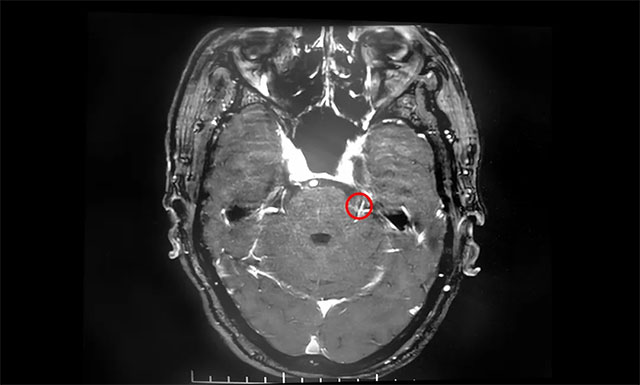

▲ 患者左側三叉神經根部與小血管關系密切

在蔡司顯微鏡(雙熒光)下可見,患者左側三叉神經后根外側有小靜脈與其位置較為緊密,并可見兩者間放置有墊片,考慮為前次微血管減壓手術放置的墊片。沈教授小心翼翼地游離三叉神經根周圍蛛網膜,靈活操作手中纖細輕巧的顯微剪刀,剪斷約三分之一的三叉神經后根……經過近5個小時的手術,患者生命體征平穩(wěn),安返監(jiān)護室。